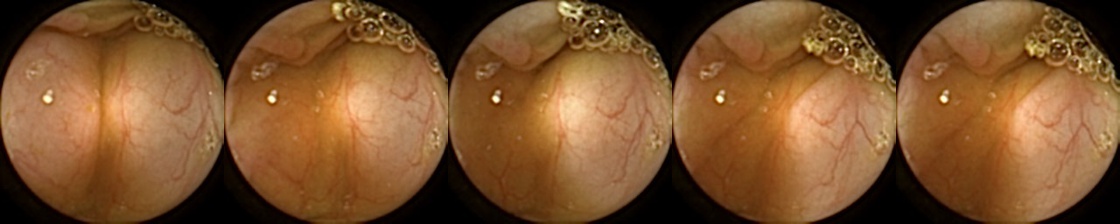

Figure 3 shows classification output examples for the MIV model using the pretrained ConvNext. Note that the model has a test accuracy of 83.66% for DBA L2 with 2 heads. In each row, the leftmost image is the query and the four images to the right of each query are the target images. The True Positive (left-top) and True Negative (bottom-right) examples outline the cases when the model is able to successfully distinguishes images containing unique polyps from those with dissimilar polyps. The False Negative (top-right) and False Positive (bottom-left) examples show the cases where the model fails to correctly distinguish images of unique polyps and images of dissimilar polyps. Further, we can note from the differences in the examples of True Positives and False Negatives that when the query image and the target set instances differ from each other in some ways, then the model can misclassify images. These differences could be attributed to different views due to the dynamics of the camera inside the colon, different views from two camera heads of the capsule, or presence of artifacts such as bubbles, debris, and small bowel secretions.

On the other hand, when we look at the examples of False Positives (Pred = true, Label = false) in Figure 3, we can note that if images in the target match the query in ways such as texture, color, illumination conditions, presence of artifacts, then this may lead to misidentification of the query as belonging to the targets. For True Negative (Pred = false, Label = false) examples, we can see that presence of significant differences between the query and the targets leads to correct identification of the image sets as different.

True Positive False Negative

Refer to caption Refer to caption

False Positive True Negative

Figure 3: True Positives (Pred = true, Label = true), False Negatives (Pred = false, Label = true), False Positives (Pred = true, Label = false), True Negatives (Pred = false, Label = false) for the DBA L2(h=2) model using the pretrained ConvNeXt. In each row, the leftmost image is the query and the 4 images to the right of each query are the target images.